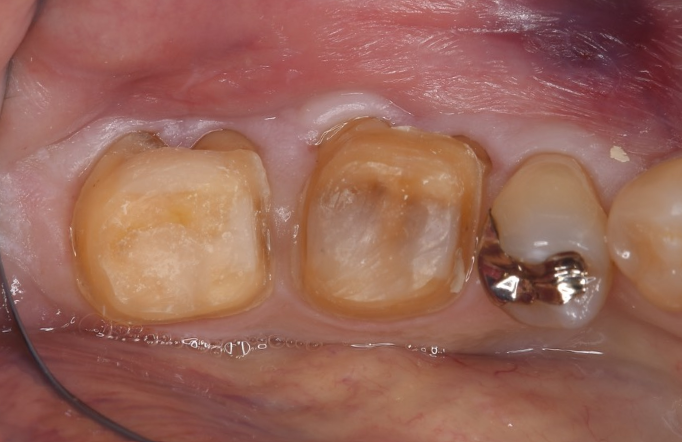

症例3

| 項目 | 詳細 |

|---|---|

| 患者様データ | 40代 女性 |

| 来院時の主訴 | 「歯がグラグラする。」 |

| 医院の診断 | 重度の歯周病、夜間歯ぎしり習慣 |

| 通院期間 |

1年 |

| 来院回数 | 8回 |

| 治療費 | 総額:220,000円(税抜) 【内訳】 歯周組織再生療法220,000円(費用は範囲によって異なります。) |

| リスクと副作用 | メインテナンスが必要、正しい歯磨き習慣が必要不可欠 |

| ここがこだわりのポイント!☝ | 痛みや手術時間が最小限となるよう、マイクロスコープを使用して小さい傷口の術式でオペを行なっています。 |